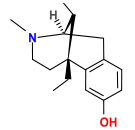

Oripavine derivatives

Thienorphine

- 7-PET

- Acetorphine

- Alletorphine (N-allyl-noretorphine)

- BU-48

- Buprenorphine

- Buprenorphine-3-glucuronide

- Cyprenorphine

- Dihydroetorphine

- Etorphine

- Homprenorphine

- 18,19-Dehydrobuprenorphine (HS-599)

- N-cyclopropylmethylnoretorphine

- Nepenthone

- Norbuprenorphine

- Norbuprenorphine-3-glucuronide

- Thevinone

- Thienorphine

Structures

| Oripavine derivatives | ||||

|---|---|---|---|---|

7-PET 7-PET |

Acetorphine Acetorphine |

Alletorphine Alletorphine |

BU-48 BU-48 |

Buprenorphine Buprenorphine |

Cyprenorphine Cyprenorphine |

Dihydroetorphine Dihydroetorphine |

Etorphine Etorphine |

Homprenorphine Homprenorphine |

18,19-Dehydrobuprenorphine 18,19-Dehydrobuprenorphine |

N-cyclopropylmethylnoretorphine N-cyclopropylmethylnoretorphine |

Nepenthone Nepenthone |

Norbuprenorphine Norbuprenorphine |

Thevinone Thevinone |

Thienorphine Thienorphine |